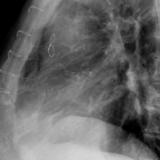

Cardiomegaly, esp RA Lat

Date: 01/26/2009

Views: 3037